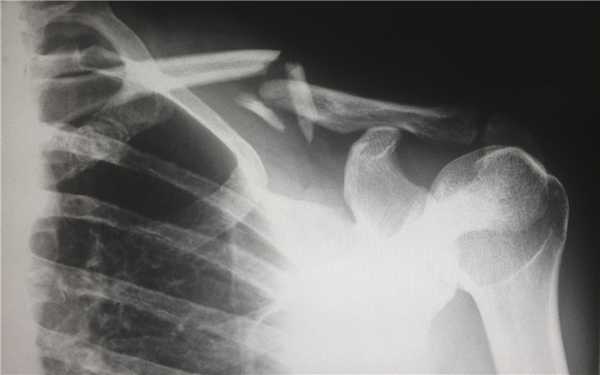

Компьютерная томография (КТ, или МСКТ) является наиболее информативным методом визуальной оценки посттравматических изменений костей, суставов и окружающих тканей. В отличие от других видов лучевой диагностики, при КТ тело человека сканируется поперечно тонкими срезами, на сканах визуализируются ткани различной морфологической структуры (кости, внутренние органы, системы кровообращения и лимфотока), а на основании полученных изображений создается трехмерная модель-реконструкция исследуемой части тела и сканы в трех плоскостях.

Таким образом, будучи пространственным, а не плоскостным (как рентген) методом визуализации любых костных анатомических структур, КТ позволяет достоверно определить тип травмы, увидеть возможные осложнения и повреждения соседних тканей. Поэтому среди врачей это исследование считается предпочтительным для диагностики переломов, особенно осложненных, в том числе внутрисуставных, не рутинных. Плюсом КТ также является оперативность и простота обследования для пациента.

Компьютерная томография позволяет детально визуализировать кости, суставы и окружающие ткани в режиме 3D, что делает этот метод идеальным для диагностики переломов разной степени сложности. Врач-рентгенолог увидит даже небольшое смещение костей, сколы и трещины, а также сможет точно рассчитать любые отклонения с помощью программного обеспечения. На трехмерной реконструкции отсутствуют артефакты (искажения), так что врач сможет точно и достоверно описать результат в заключении.

На КТ в высоком разрешении будут видны деструктивные и воспалительные процессы в костях, суставах и, что не менее важно, в прилегающих тканях. Квалифицированный врач-травматолог, хирург или другой специалист сможет не только ознакомиться с письменным заключением, но и изучить КТ-сканы.

Алгоритм диагностики переломов обычно таков, что сначала пациента осматривает врач-травматолог, после отправляет пострадавшего на рентген. Исключением являются заведомо диагностически сложные случаи, когда предпочтение сразу отдается КТ — переломы черепа (смотрим головной мозг), позвонков (смотрим спинной мозг), тазобедренного (самый подвижный) и коленного сустава (самый сложный), особенно при подозрении на внутрисуставной перелом.